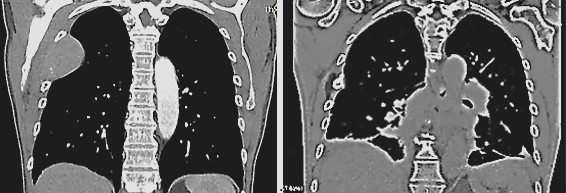

After five years of being free of symptoms, a rapidly growing, parotid-adjacent tumor on the right side occurred leading to facial palsy. An attempt to surgically remove the tumor was aborted due to risk to the facial nerve. An F-18-FDG PET whole-body CT scan revealed several disseminated hepatic metastases, osseous metastases in the pelvis and in the 5th dorsolateral rib. Histology of a biopsy from a hepatic metastasis as well as from a biopsy of the osteolytic region at the 5th rib, confirmed a recurrence of malignant melanoma. At this moment, the patient was in significantly reduced general condition with bad prognosis. The patient has been receiving oncological combination therapy with two immune checkpoint inhibitors, Ipilumab and Nivolumab. In parallel, an ultrasound-guided, once-weekly piezoelectric TMI treatment in the right parotid region was initiated. For this purpose, the PiezoWave2 device was used with a gel pad (shallow penetration depth Gelpad Nos. 5 and 10). The frequency used was between 2 and 4 Hz per treatment, with 3 Hz being the most common frequency. Depending on pain sensitivity and tolerance, 1000-1500 impulses were applied per session with an energy flux density of 0.12 mJ/mm². Following four immune checkpoint combination therapy sessions and eleven treatments with piezoelectric TMI treatment, a distinct regression after two months and a complete remission of the parotid-adjacent tumor as well as complete concomitant remission of the facial palsy occurred within four months (Fig. 3). Alongside the TMI treatment of the parotid region, TMI treatment of the pelvis metastasis using the PiezoWave2 device was performed simultaneously, precisely localizing the metastatic area measured in the PET-CT scan and based on patient-specific FEM simulation analyses. The deepest penetration depth was achieved with Gelpad 60, at a frequency of 2 Hz. Each treatment delivered 3000 impulses with an energy flux density of 0.35 mJ/mm². In a CT scan six months later, a significant reduction in bone metastases was observed as well as a complete remission of the hepatic metastases not directly treated with shock waves; however, a new pelvic metastasis had occurred. The metastasis at the 5th rib had disappeared (Fig. 4). Though the patient was affected by both the oncological disease and the side effects of the drug therapy, to consolidate and continue the evident therapeutic efficacy, regular TMI treatment of the new metastasis in the pelvic region was resumed with the OrthoGold100® device. The patient was treated 14 times over a six-month period. Each treatment involved a combination of the focused technique with the dark blue applicator and the non-focused technique with the yellow applicator. The deepest penetration depth was selected, along with energy flux density of 0.18 mJ/mm² or 0.27 mJ/mm², applying 2000 impulses per applicator, thus a total of 4000 impulses per session. After TMI treatment, native CT scans showed a distinct regression of the new pelvic metastasis and unchanged sclerosis of the known bone metastases.

Fig. 4

Fig. 4: Metastasis at the 5th rib before TMI treatment (left) and disappearance of the metastasis six months after TMI treatment (right).